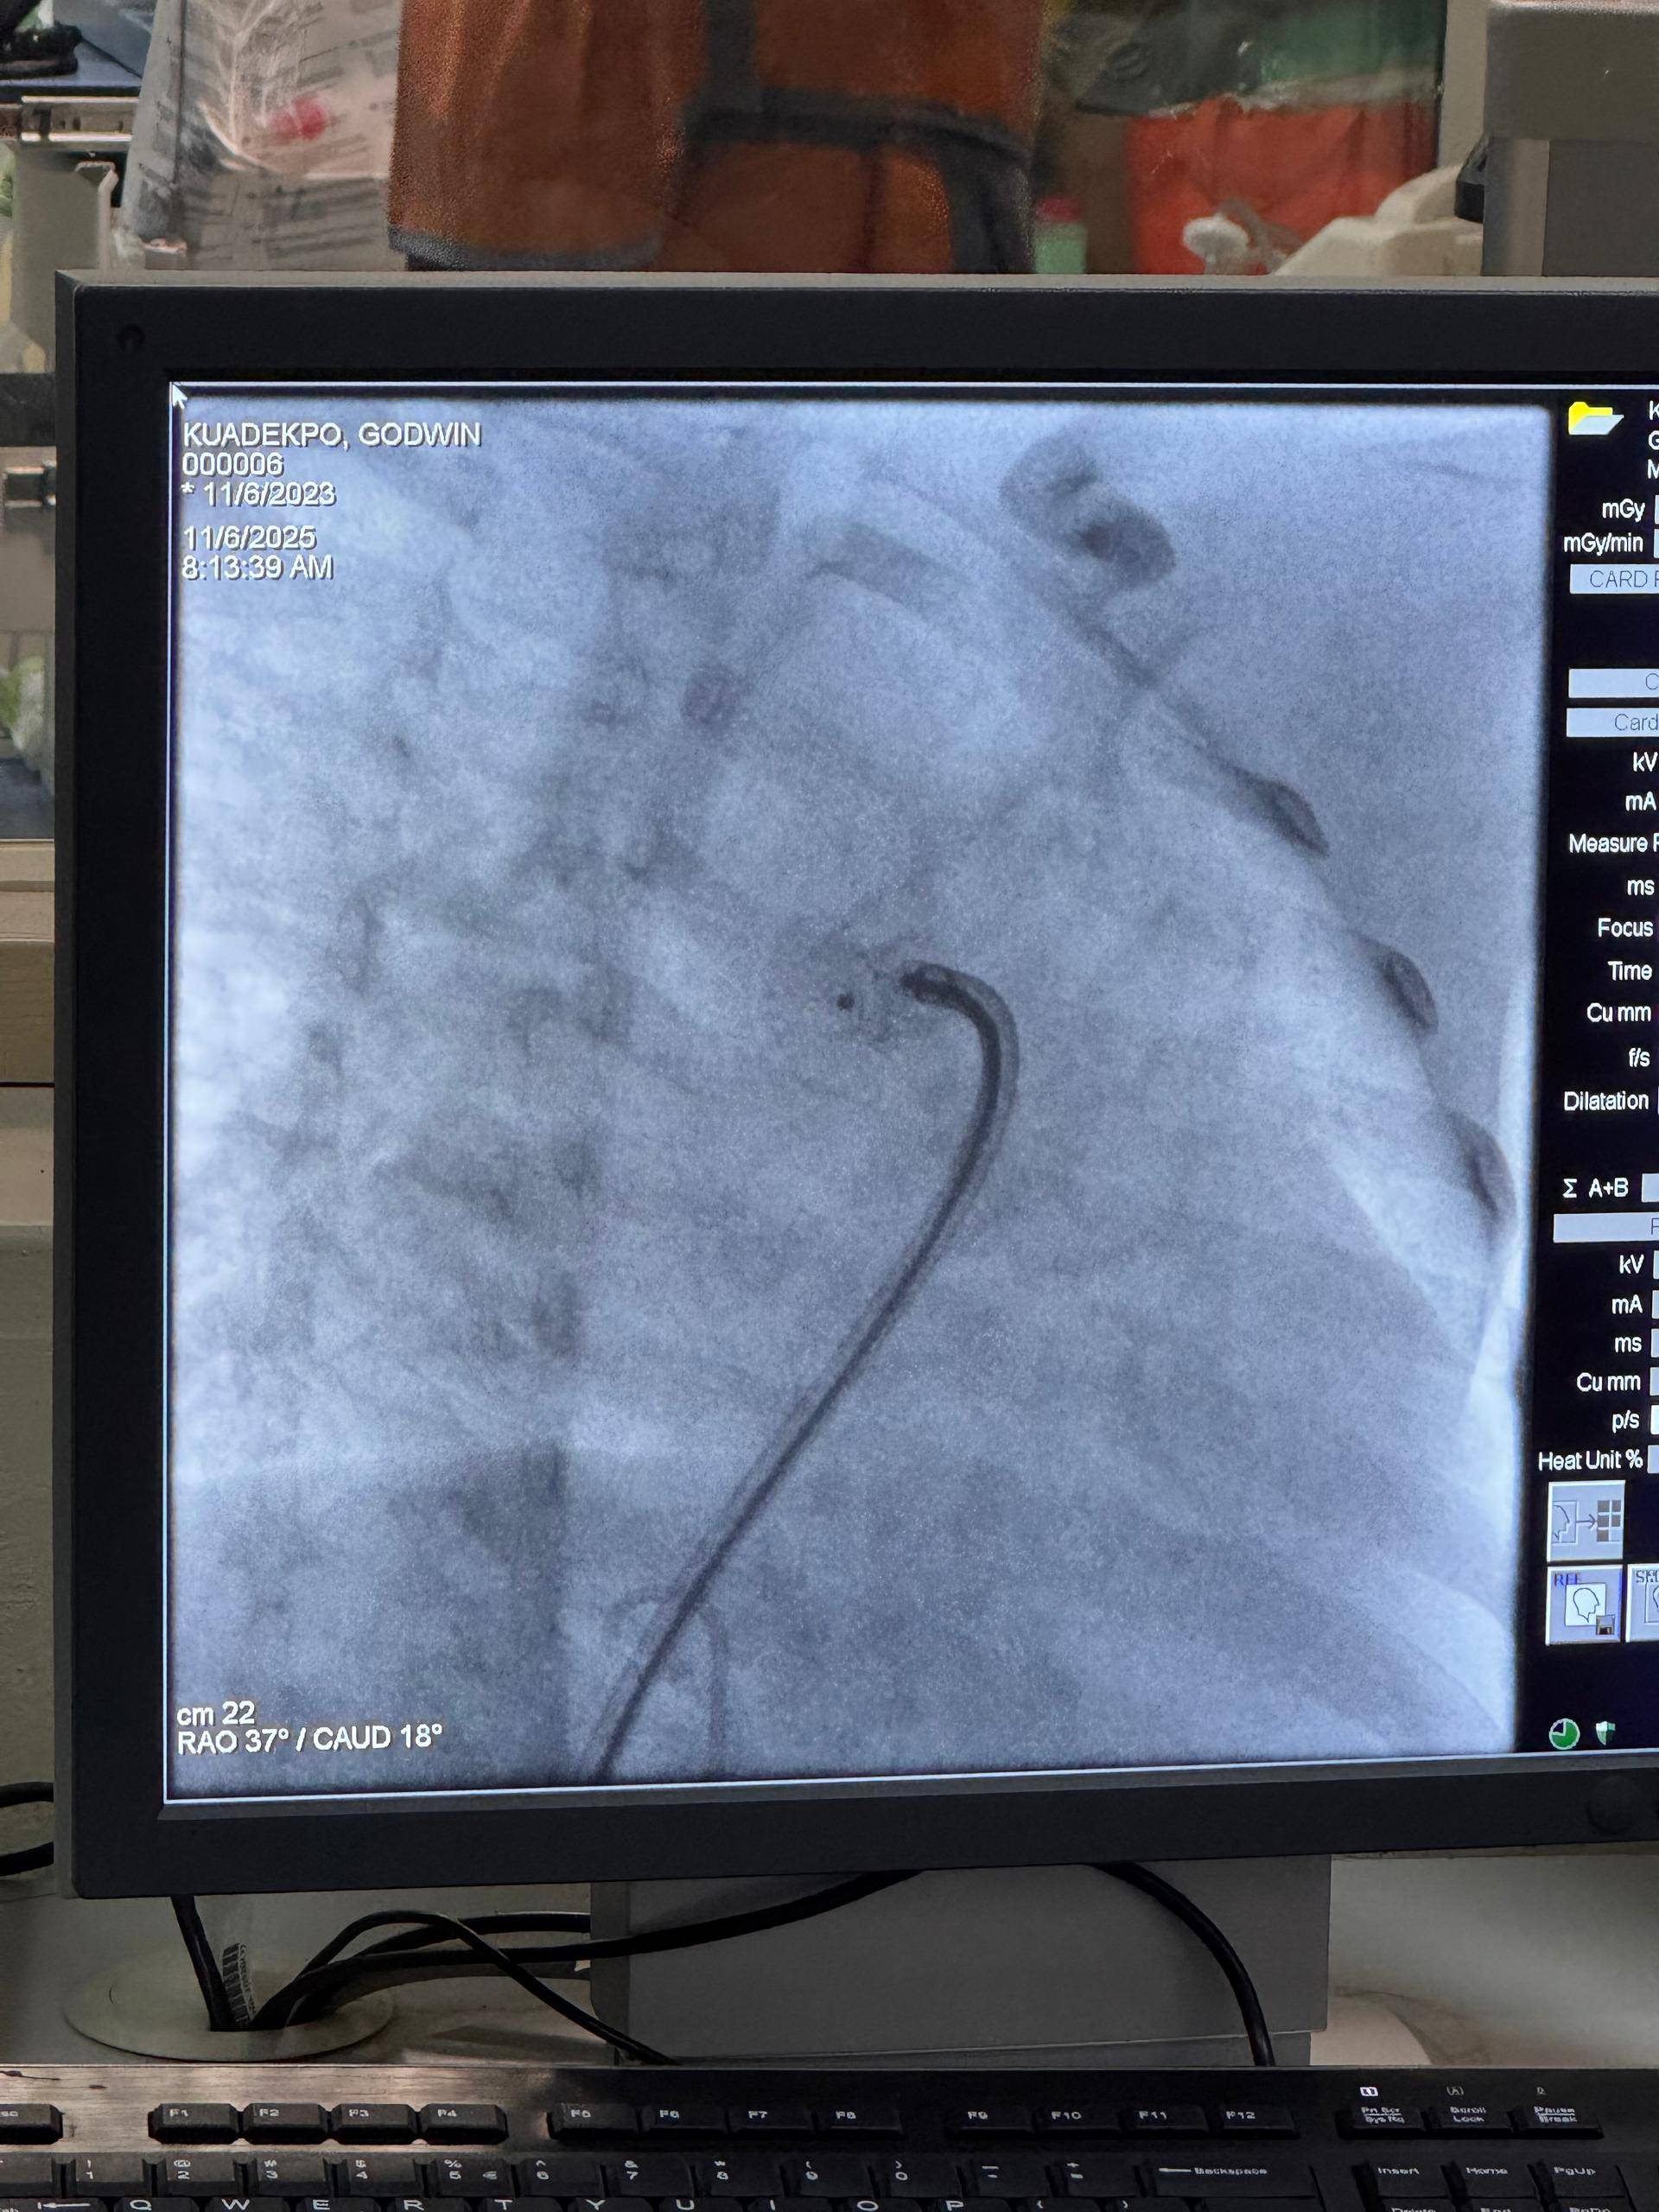

Beide zeigten sich tief beeindruckt von der Professionalität, dem Engagement und der Menschlichkeit des gesamten Teams. Seit vielen Jahren unterstützt die Stiftung mit Ärzten und Pflegekräften aus Deutschland Kinder in Ghana, die an angeborenen Herzfehlern leiden – und schenkt ihnen durch lebensrettende Operationen neue Hoffnung.

„Gestern durfte ich im Korle-Bu Teaching Hospital den Ärzt:innen und Pfleger:innen der Gerald Asamoah Stiftung für herzkranke Kinder über die Schulter schauen. Ich habe großen Respekt vor der Arbeit, die sie dort leisten – engagiert, professionell und mit so viel Herz. Ich war sehr berührt.💖“